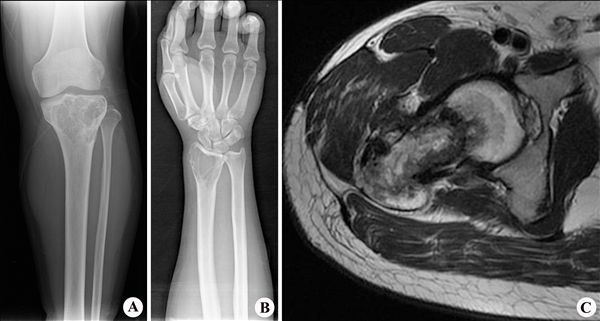

【影像表现】:X线胫骨正位(A)示胫骨上端呈膨胀性骨质破坏;腕关节X线正位(B)示桡骨远端皂泡样改变,边缘清楚;MRI T2WI(C)示右侧股骨上段小片状混杂信号。

【影像诊断】:骨巨细胞瘤。